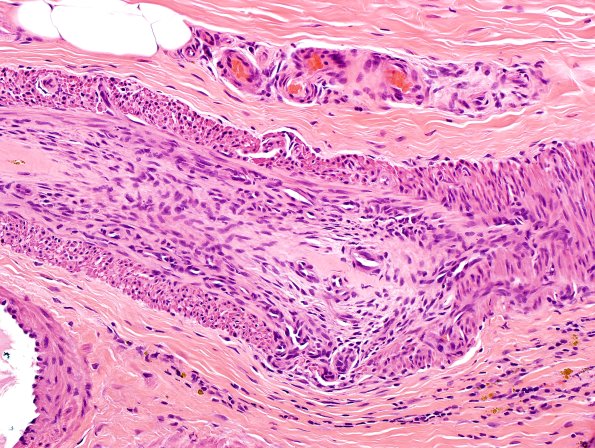

9A2,3 Higher magnification images showing disorganization of the vascular walls and recanalization of the thrombosed vessels. (H&E)